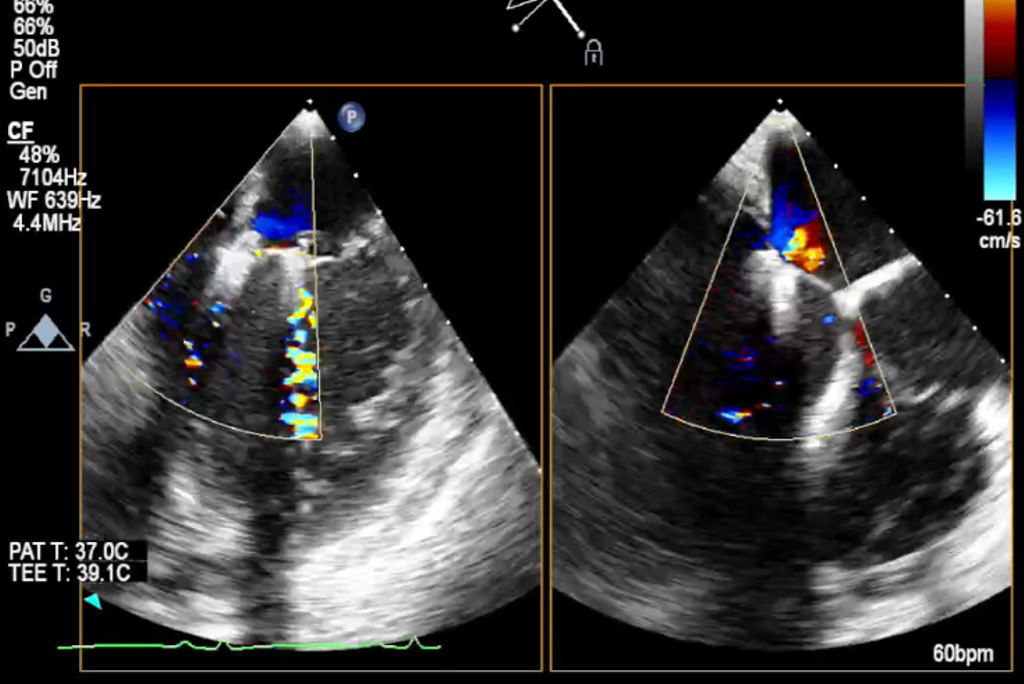

术前TEE显示二尖瓣重度反流,反流主要来源于A2/P2区

患者全麻状态下,在经食道超声心动图和X射线透视引导下,采用股静脉入路,将申淇淇麟®系统瓣膜夹顺利送至二尖瓣A2/P2区域,经调整位置使瓣膜夹垂直对合缘后跨瓣。应用申淇淇麟®系统单瓣叶独立捕获功能,先后捕获二尖瓣前叶和后叶。经超声心动图反复确认瓣叶夹持牢固, A2/P2区域反流量减少,瓣膜夹M侧(3区)残余少量反流。经手术小组专家讨论,决定在M侧植入第二枚瓣膜夹。第二枚瓣膜夹植入之后,经超声心动图反复确认瓣叶夹持牢固,二尖瓣反流减少,跨瓣压差为3mmHg。释放后,经超声心动图和DSA影像评估,双瓣膜夹均夹持稳定,位置和功能良好,效果满意。这一颇具难度的病例手术获得圆满成功。

TEE显示,二尖瓣夹植入后反流减少